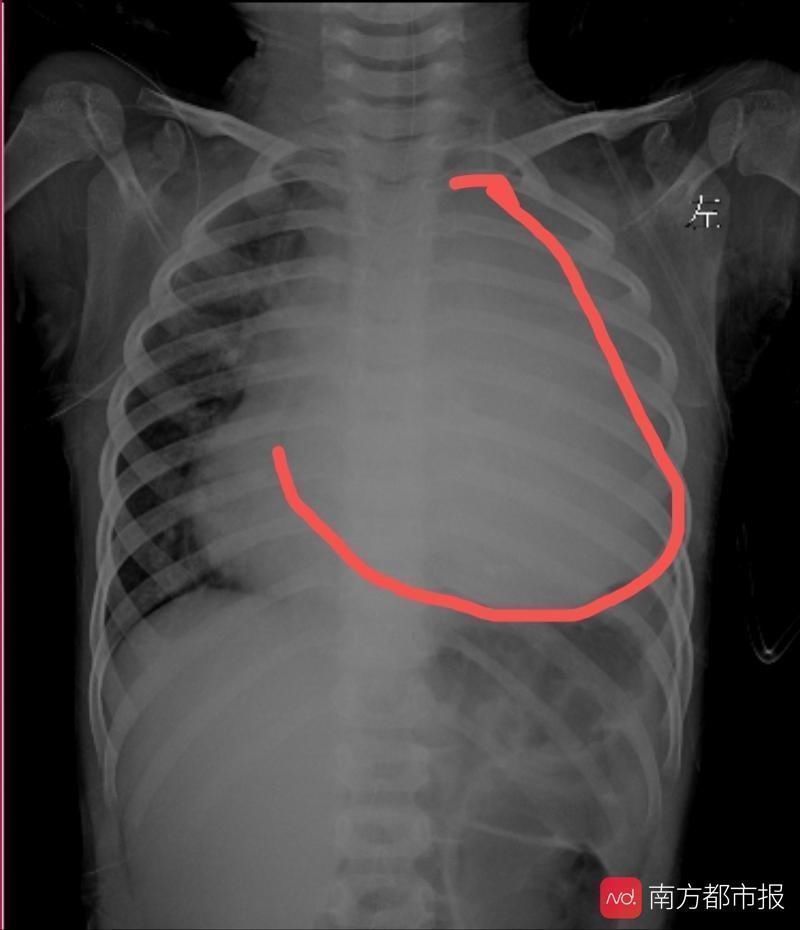

11月8日,3岁8个月的小星星因“发热伴咳嗽2周”入住中山大学附属第一医院。她在2周前无明显诱因出现发热,最高达39℃,伴咳嗽,呈刺激性干咳。检查发现原来致病的元凶是胸腔内长了一个11cm的巨大肿瘤,肿瘤完全占据了整个左侧胸腔,心脏、大血管和左肺完全被挤压到了对侧。

手术前,小星星的左侧胸腔已经被完全挤占